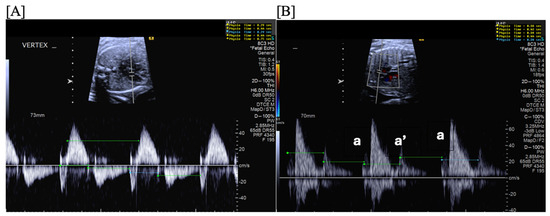

- Short VA SVT (Figure 3 and Figure 4) demonstrates a ventricular–atrial (VA) interval that is less than half of the ventricular–ventricular (VV) interval (VA:AV ratio < 1) and a sudden onset and termination of tachycardia; tachycardia usually terminates with a non-conducted atrial contraction. Short VA SVT includes AVRT (also known as orthodromic reciprocating tachycardia, ORT) and atrioventricular nodal reentrant tachycardia (AVNRT). Short VA SVT typically presents after 18 weeks of gestation.